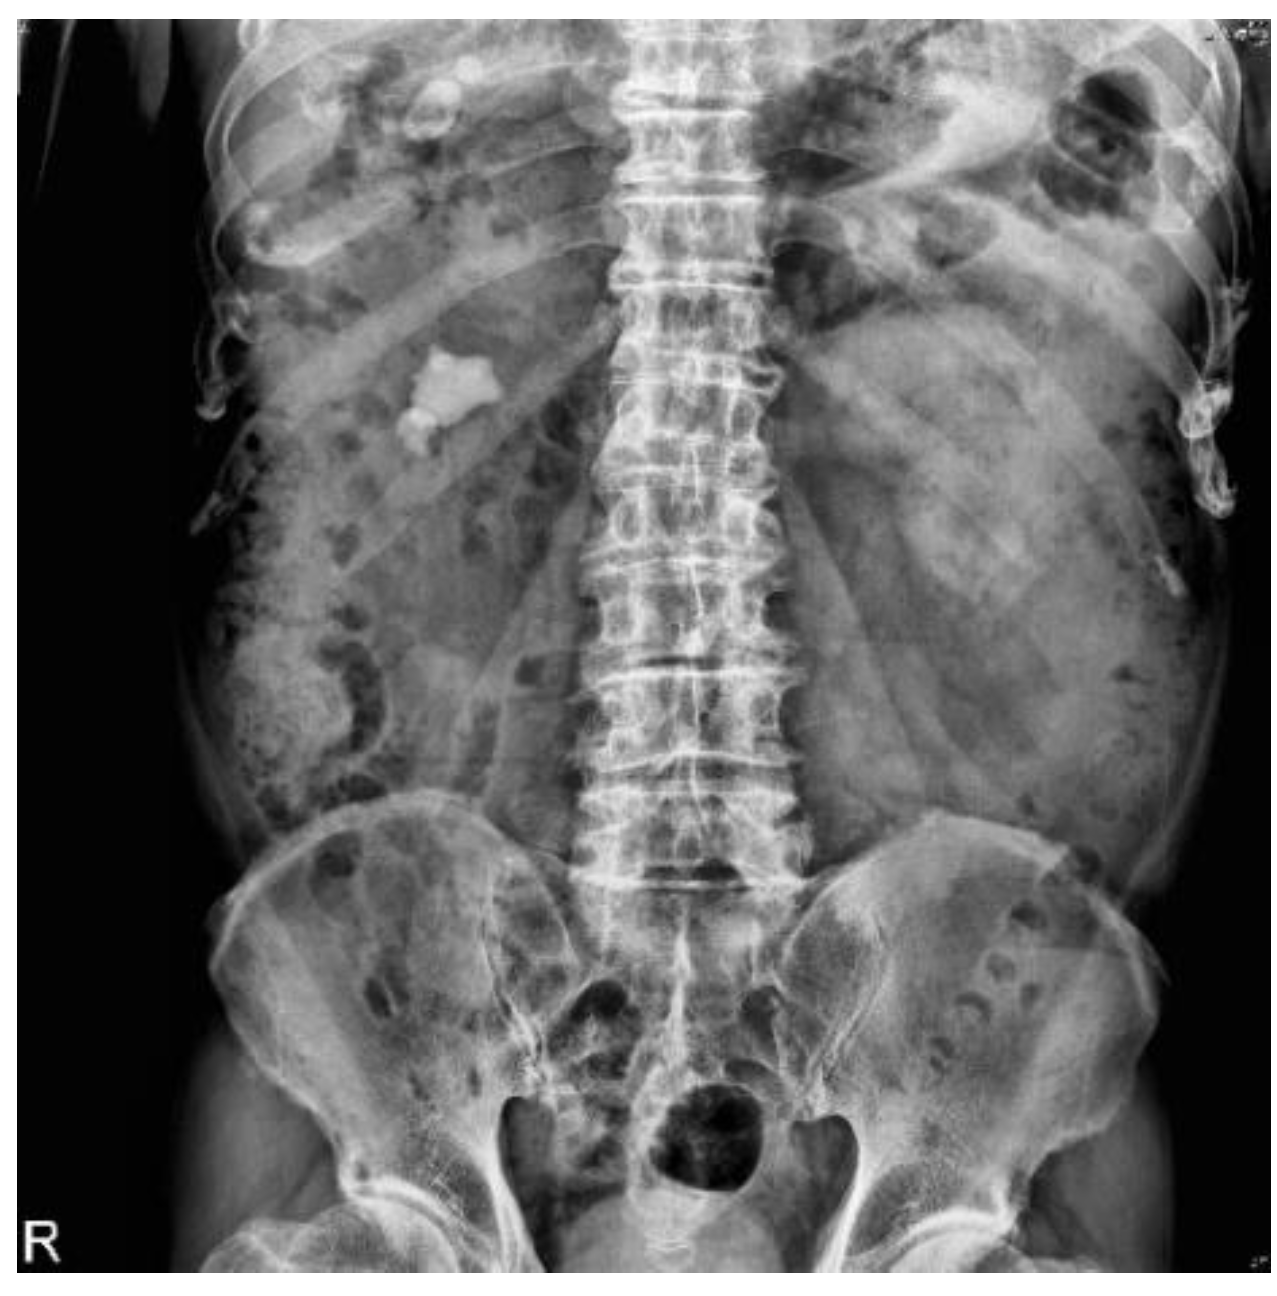

2.2. Datasets

2.3. Image Preprocessing

2.3.1. Contrast-Limited Adaptive Histogram Equalization